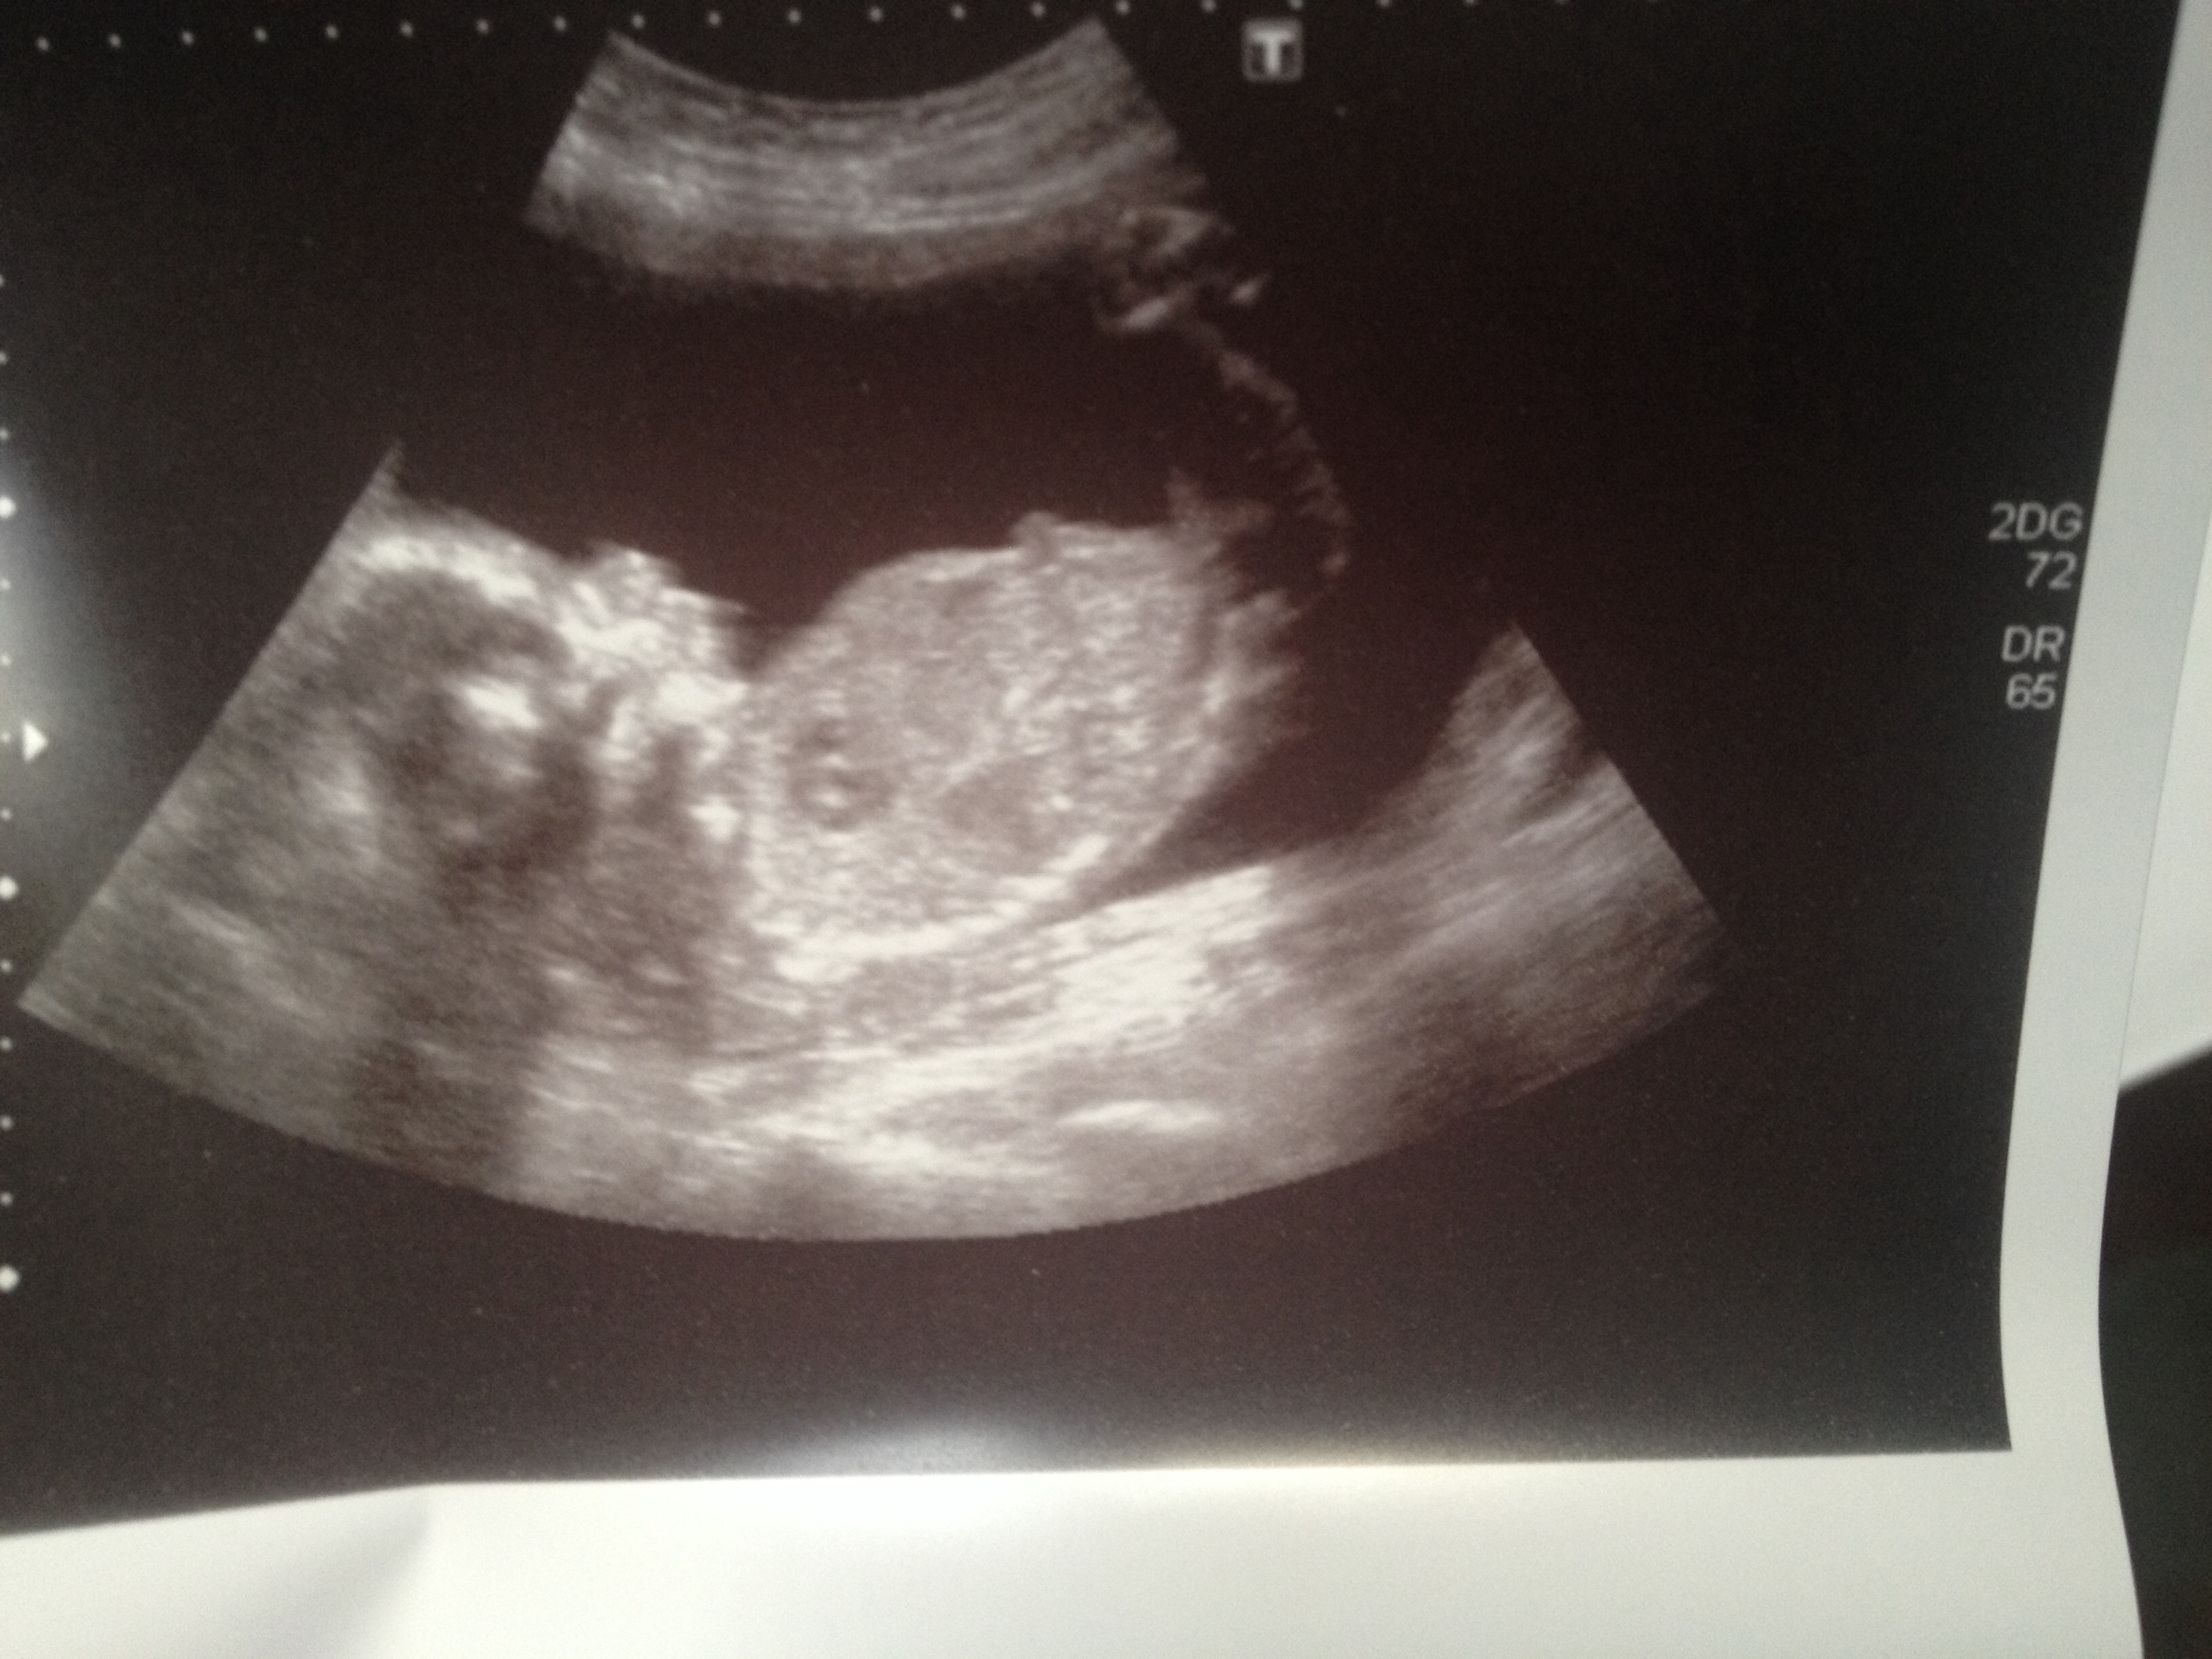

Need help is this boy?! 20week scan

Leaning girl, I think. Congrats! x

I am thinking boy!